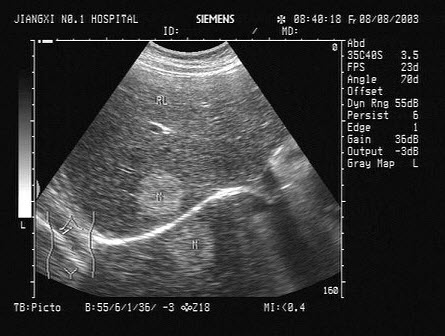

12、单项选择题

男性,70岁,左下肢橡皮肿,阴囊肿大如橄榄球大小,阴囊壁增厚,B超声像图如下,患者有可能是下列哪个疾病()

A.丝虫病